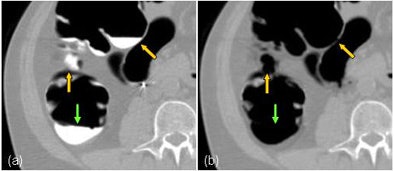

| Illustration of the artifact of false fistula in electronic cleansing. The thin haustral folds sandwiched by the tagged regions and the lumen, called tagging-tissue-air layers (orange arrows, left image), are erroneously removed as the boundaries between lumen and tagged materials (such as the ones indicated by the green arrows), creating false fistulae as indicated by the orange arrows on the right image. |